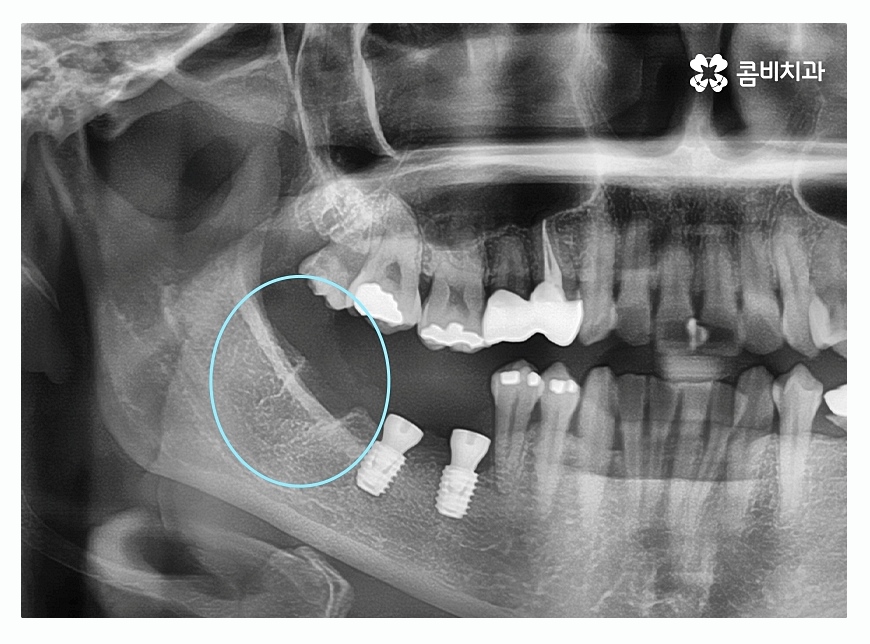

오늘 보시는 환자분의 경우에는 치주질환이 심해져서

여러 치아를 발치하게 된 사례로 자연치아의

수명을 다하지 못한 채 발치를 하는 것은 안타까운 일이지만

치주질환 관리를 제대로 하지 못할 경우에는

노년에 이르러 치아를 모두 상실하게 되는 경우도

많기 때문에 중년 이후에는 특히 주의할 필요가 있어요.

위 이미지에서 보시는 것처럼 치주염으로 인하여

잇몸뼈가 많이 내려간 경우 음식물이 잘 끼고 관리가 잘 안되면서

치아가 깊게 뿌리내리지 못해 흔들리게 되고

치아가 제대로 된 기능을 하지 못하여 발치까지 진행되는 경우가 있는데

위 환자분도 사랑니가 이런 경우에 해당되어 발치를 진행한 사례라고 할 수 있어요.